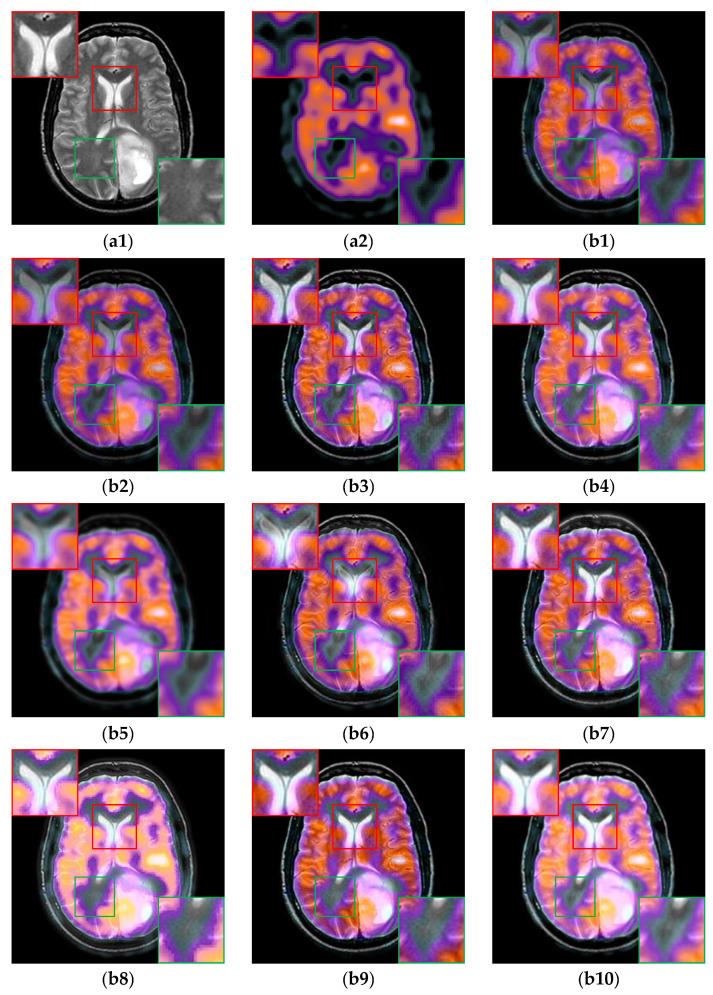

Multi-modal medical image fusion (MMIF) is crucial for disease diagnosis and treatment because the images reconstructed from signals collected by different sensors can provide complementary information. In recent years, deep learning (DL) based methods have been widely used in MMIF. However, these methods often adopt a serial fusion strategy without feature decomposition, causing error accumulation and confusion of characteristics across different scales. To address these issues, we have proposed the Coupled Image Reconstruction and Fusion (CIRF) strategy. Our method parallels the image fusion and reconstruction branches which are linked by a common encoder. Firstly, CIRF uses the lightweight encoder to extract base and detail features, respectively, through the Vision Transformer (ViT) and the Convolutional Neural Network (CNN) branches, where the two branches interact to supplement information. Then, two types of features are fused separately via different blocks and finally decoded into fusion results. In the loss function, both the supervised loss from the reconstruction branch and the unsupervised loss from the fusion branch are included. As a whole, CIRF increases its expressivity by adding multi-task learning and feature decomposition. Additionally, we have also explored the impact of image masking on the network's feature extraction ability and validated the generalization capability of the model. Through experiments on three datasets, it has been demonstrated both subjectively and objectively, that the images fused by CIRF exhibit appropriate brightness and smooth edge transition with more competitive evaluation metrics than those fused by several other traditional and DL-based methods.

多模态医学图像融合(MMIF)对于疾病诊断和治疗至关重要,因为从不同传感器收集的信号重建的图像可以提供互补信息。近年来,基于深度学习(DL)的方法已广泛应用于MMIF。然而,这些方法通常采用无特征分解的串行融合策略,导致误差累积和不同尺度特征的混淆。为了解决这些问题,我们提出了耦合图像重建与融合(CIRF)策略。我们的方法将图像融合和重建分支并行,通过一个公共编码器连接。首先,CIRF使用轻量级编码器分别通过视觉Transformer(ViT)和卷积神经网络(CNN)分支提取基础特征和细节特征,两个分支相互作用以补充信息。然后,两种类型的特征分别通过不同的模块进行融合,最后解码为融合结果。在损失函数中,既包括来自重建分支的监督损失,也包括来自融合分支的无监督损失。总体而言,CIRF通过添加多任务学习和特征分解提高了其表达能力。此外,我们还探讨了图像掩码对网络特征提取能力的影响,并验证了模型的泛化能力。通过在三个数据集上的实验,主观和客观地证明了,与其他几种传统方法和基于DL的方法融合的图像相比,CIRF融合的图像具有适当的亮度和平滑的边缘过渡,评估指标更具竞争力。